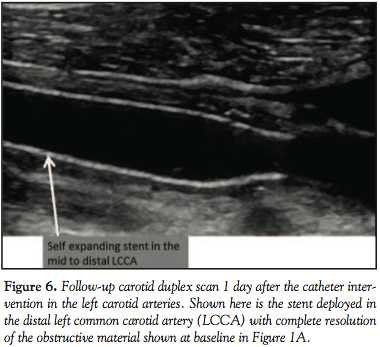

There were no new neurologic changes the following day and a carotid duplex scan showed no residual thrombus (Figure 6).